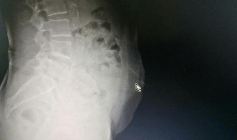

文章图片

影像显示阿婆断针的位置 。

为了确认针的位置 , 尽快把针取出 , 副主任医师潘裕国对患者做了CT定位和三维重建 , 发现针已从皮下组织扎到了腹直肌里 , 万幸未伤及内脏 。